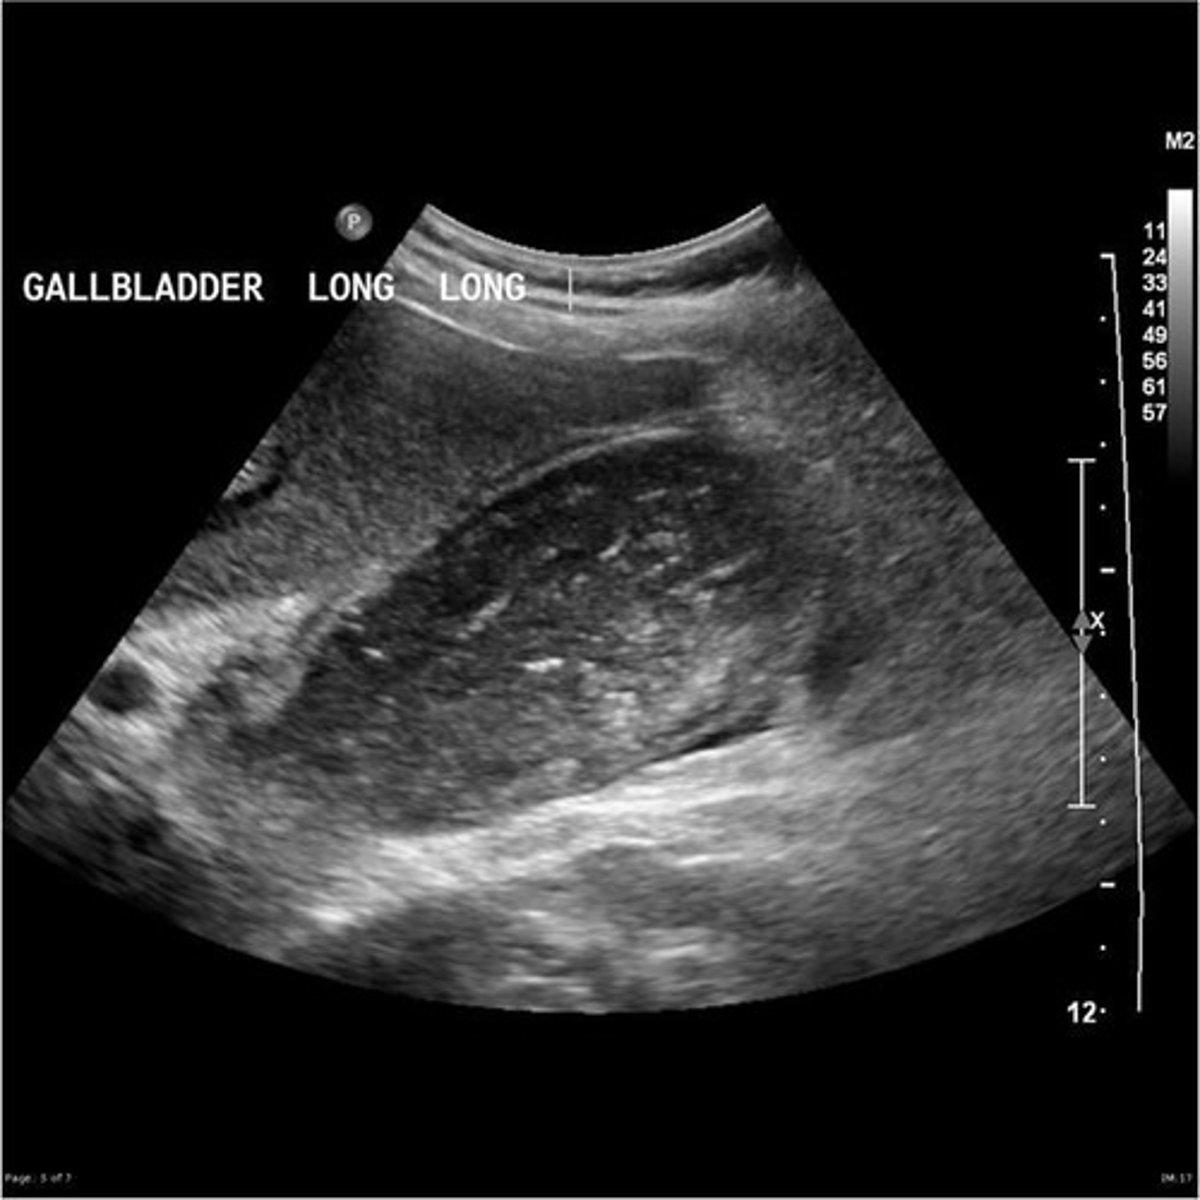

gallbaldder carcinoma

-rare

-caused by chronic inflammation of the GB wall by stones

-associated with gallstones in 80-90% of cases

-mass may contain gallstones

- tumor arises in BODY of GB

-mass most often fills the entire GB!!!

Who is at an increased risk of developing gallbladder carcinoma?

patients with chronic cholecystitis and women 60+